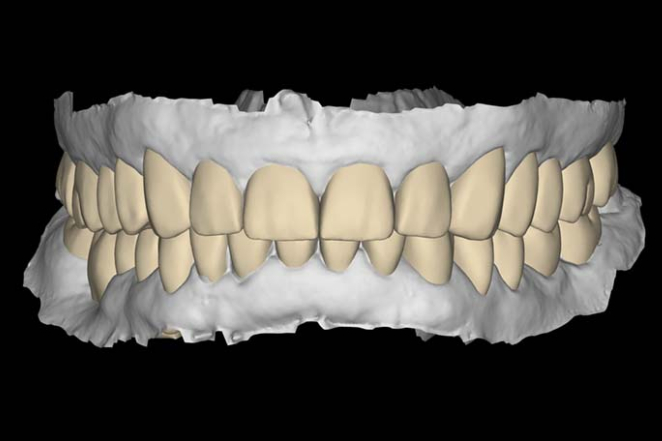

Cyfrowe projektowanie uśmiechu to nowoczesny sposób planowania leczenia stomatologicznego, który pozwala zobaczyć przyszły efekt jeszcze przed rozpoczęciem odbudowy zębów. Dzięki wykorzystaniu technologii cyfrowych możliwe jest precyzyjne zaplanowanie zarówno estetyki uśmiechu, jak i funkcji całego narządu żucia.

W Rehadent wykorzystujemy nowoczesne technologie cyfrowe, które pomagają dokładnie analizować warunki zgryzowe oraz planować leczenie w bardziej przewidywalny i precyzyjny sposób. Pacjent może aktywnie uczestniczyć w procesie projektowania przyszłego uśmiechu jeszcze przed rozpoczęciem właściwego leczenia.

Cyfrowe projektowanie uśmiechu pozwala dokładniej zaplanować zarówno estetykę, jak i funkcję przyszłej odbudowy zębów.

Na podstawie zebranych danych przygotowywany jest cyfrowy projekt przyszłego uśmiechu. Pozwala on wcześniej zobaczyć planowany efekt leczenia, omówić możliwe rozwiązania oraz wprowadzić ewentualne zmiany jeszcze przed rozpoczęciem właściwej odbudowy zębów.

Cyfrowe projekty przygotowywane są we współpracy lekarza oraz pracowni protetycznej Goldlab. Projektowanie wykonywane jest cyfrowo w systemie Exocad, co pozwala dokładnie planować przyszły wygląd i funkcję odbudowy. Finalne prace opracowywane są z dbałością zarówno o estetykę uśmiechu, jak i prawidłową funkcję zgryzu.